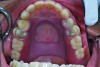

A 65-year-old Caucasian male presented for treatment at the University of North Carolina Dental Faculty Practice. The patient’s chief complaint was the appearance of his teeth, which looked short and had insufficient display when he smiled. The patient was partially edentulous in both the maxillary and mandibular arches and was wearing a cast mandibular RPD and a maxillary interim acrylic RPD. Findings from the clinical and radiographic examinations revealed moderate tooth wear on the posterior teeth and prepared maxillary canines without overlying extracoronal restorations. The prepared teeth were discolored, but no caries was detected clinically when examined using a caries detection solution. Also, the maxillary right first premolar had a coronal fracture and significant tooth wear. The prepared canine teeth were vital with limited interocclusal clearance available for any restorative material at the existing OVD (Figure 14).

The patient’s existing removable prostheses were evaluated clinically. The prosthetic teeth on both RPDs were worn, and after the OVD was assessed with the existing removable prosthesis, it was determined to be reduced significantly. Before making any decision on the type of treatment, the choice was made to first correct the OVD with an interim esthetic overlay acetal resin RPD.

Fig 14. Pre-operative condition. Notice prepared maxillary canines with limited interocclusal clearance at existing OVD mainly on the left side.